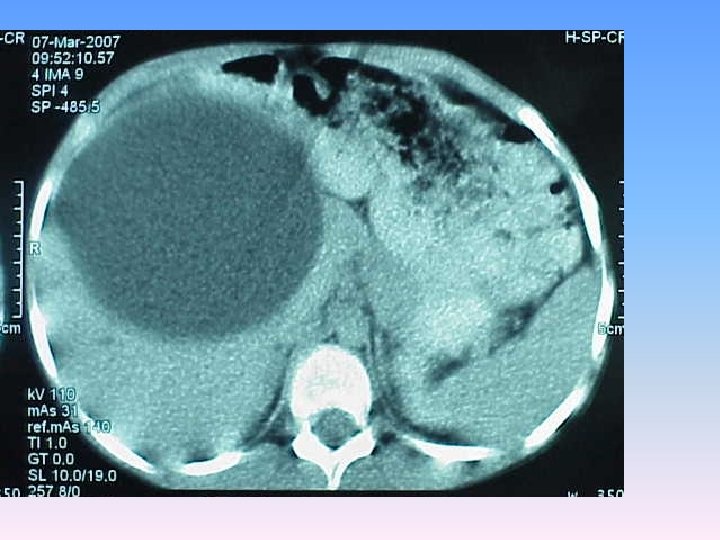

Abdominal CT Scan § A regular lobulated cystic mass in right lobe of liver (120 x 120) without calcification causing dilatation of intra & extra biliary ducts.

MRCP & MRI § Huge thicked wall cystic mass (140 x 120 mm), at the portahepatis that seems connected to biliary tree and gall bladder, resulted in severe dilatation of intra hepatic bile ducts and displaced right kidney posteriorly. § Spleen, kidneys, bowel loops and abdominal wall are normal. § Finding could be due to congenital anomalies like choledocal cyst, Duplication cyst, mesenteric cyst and hydatid cyst are in DDx.